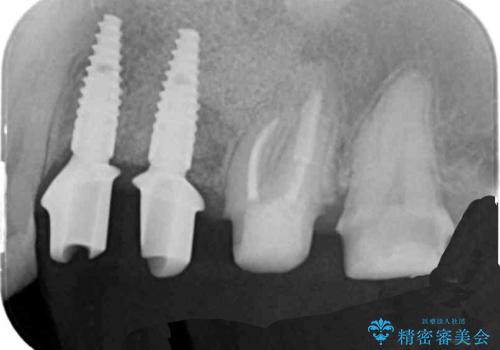

治療後に再発した虫歯や根管再治療に加え、穴の空き症状のある上顎左側小臼歯は抜去を行いインプラントによる機能回復治療を計画します。

X線写真検査ではわからない虫歯も外してみると再発していることがあります。虫歯を丁寧に取り除き、再発を防ぐべく精密なクラウンの作製を行うことが長期的な予後につながります。